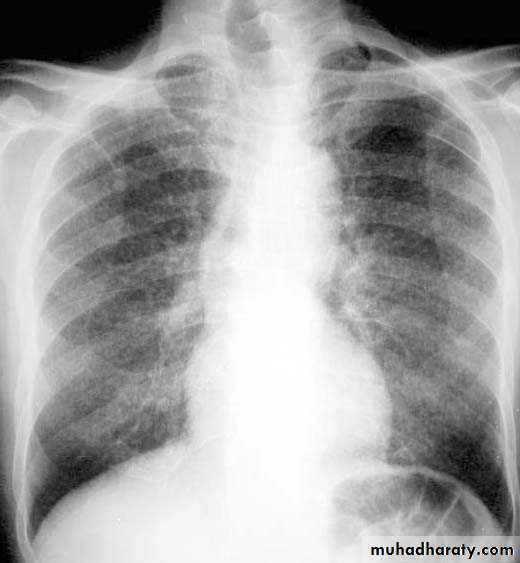

NORMAL PA view